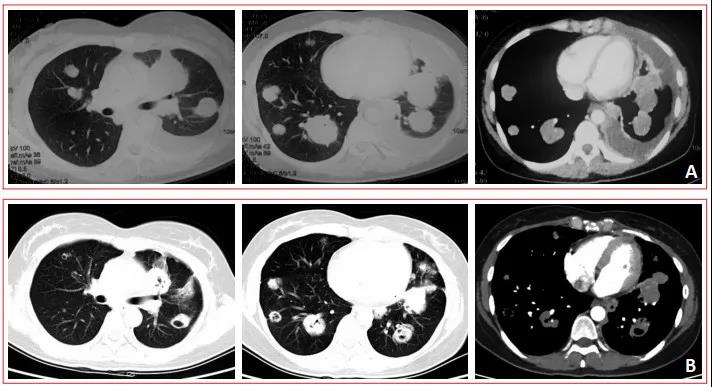

卡瑞利珠单抗联合安罗替尼治疗鼻咽癌1例林建光 康艺苹 许天文 ( 福建医科大学 附属第二医院)01 病例简介患者,女性,34岁。2017年5月于福建医科大学附...